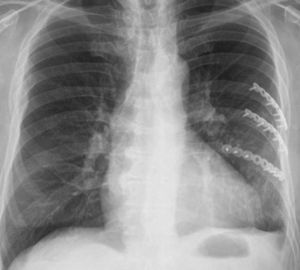

Casos clínicosCaso 1Paciente masculino de 61 años con antecedente de trauma cerrado de tórax al ser arrollado por un toro, trasladado al servicio de urgencias en donde entró en falla respiratoria por lo cual es intubado, requiriendo ventilación mecánica. En la valoración inicial se identificó gran deformidad de la pared torácica anterior izquierda con tórax inestable asociada a enfisema subcutáneo. En la radiografía de tórax se documentó neumotórax izquierdo, por lo que se realiza una toracostomía cerrada izquierda, y es trasladado a la unidad de cuidados intensivos; en este servicio se solicitó una tomografía axial computada de tórax que evidenció múltiples fracturas costales izquierdas desplazadas y neumotórax (fig. 1). Con estos hallazgos se pidió interconsulta a cirugía de tórax, quienes consideraron que el paciente era candidato para osteosíntesis de reja costal con placas de osteosíntesis de tercio de caña de 8 orificios con tornillos bicorticales, procedimiento que se realizó sin complicaciones con la utilización de sello de agua en el postoperatorio (fig. 2).

El paciente es extubado 6 días después, y dado de alta en el día 14 del postoperatorio, sin complicaciones. Regresó a su vida laboral después de 30 días del trauma. No hay seguimiento de la función pulmonar por pérdida del paciente.